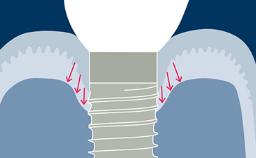

成功的种植治疗需要以修复为导向制定种植计划,以确定理想的种植体位置。种植体的位置应方便戴入理想的最终修复体,而理想的修复体应能满足功能性和美观性需求并模拟天然牙列。

通过辅助诊断检查,可确定和评估位点特定的外科和修复要求。这有助于尽量减少种植治疗后的并发症和失败风险。